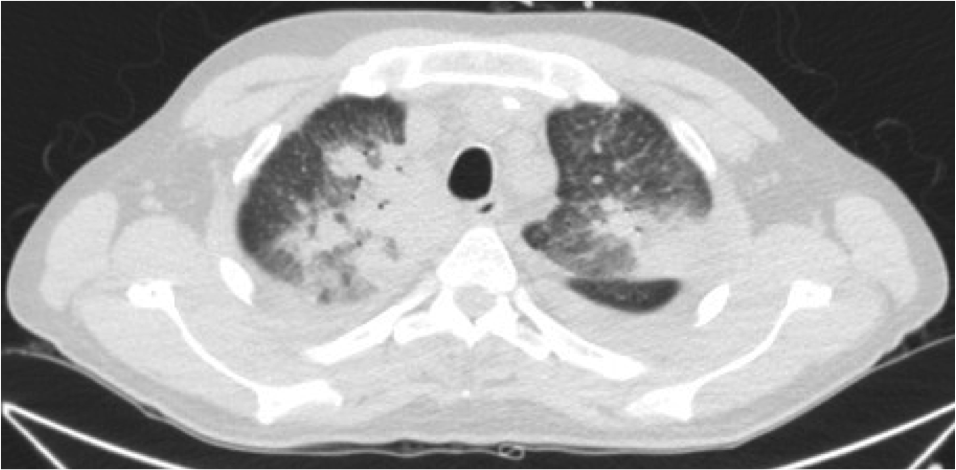

Paciente de 69 años al que se le realiza un estudio programado de TAC por presentar hemoptisis ocasionales. No refiere alteración del estado general, no sd constitucional, IMC 26. En la placa de tórax se observó una masa en LSI.

Por tanto, estamos ante un colapso crónico del LSI con lesión cavitada ocupada en su interior por una imagen redondeada compatible con Aspergiloma que podría ser el responsable de las hemoptisis ocasionales que presenta el paciente.

Presentada arriba. Subtipo caracterizado por la no ivasión de tejidos. Se caracteriza por conglomerados de hifas entrelazadas + mucus + detritus celulares, que se acumulan en una cavidad o bronquio. Se dan en áreas del pulmón con enfermedad o cicatrización previas, siendo la mayor parte de las etiologías subyacente la tuberculosis, la sarcoidosis o absceso. Suelen ser asintomáticos o dar hemoptisis.

Hallazgos radiológicos: Radiografía, masa sólida con densidad de partes blandas dentro de una cavidad. La masa está separada de la pared por aire «Air crescent sign». El aspergiloma se mueve cuando el paciente cambia de posición. (Diagnóstico diferencial: Aspergillus angioinvasiva, Equinococcus, Carinii, TBC, carcinoma, absceso, aneurismas de Rasmussen en TBC.)